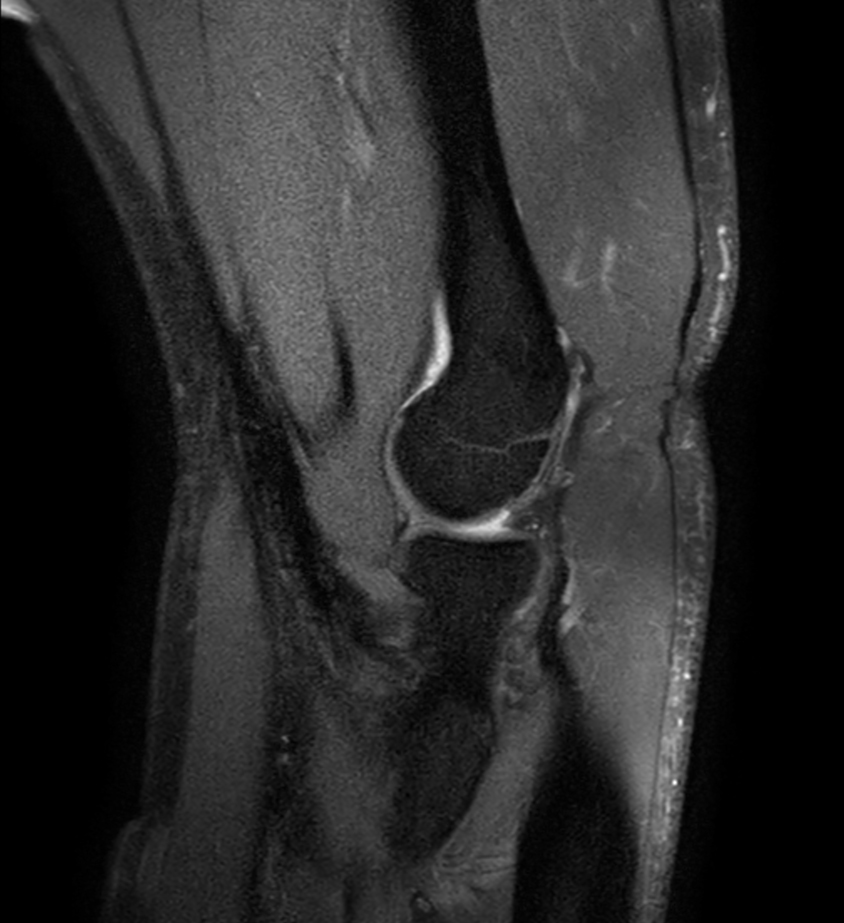

Coronal T1w mDIXON XD TSE (In Phase)